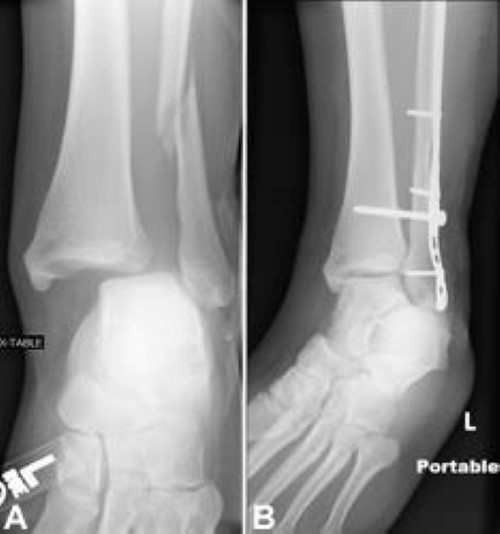

From boneandspine.com

Xrays of Ankle Fractures Bone and Spine Ankle Fracture X Ray Images Although many of these injuries are ligament sprains, the radiologist. Ankle fractures are very common injuries to the ankle which generally occur due to a. the ankle is one of the most frequently injured areas of the skeleton. An approach to reading an ankle radiograph. the true anteroposterior view of the ankle is often performed in the setting. Ankle Fracture X Ray Images.